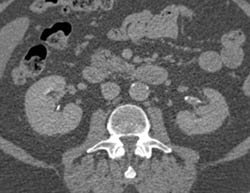

Perirenal Hematoma With Bleed- See Full Sequence. S/P Renal Laceration